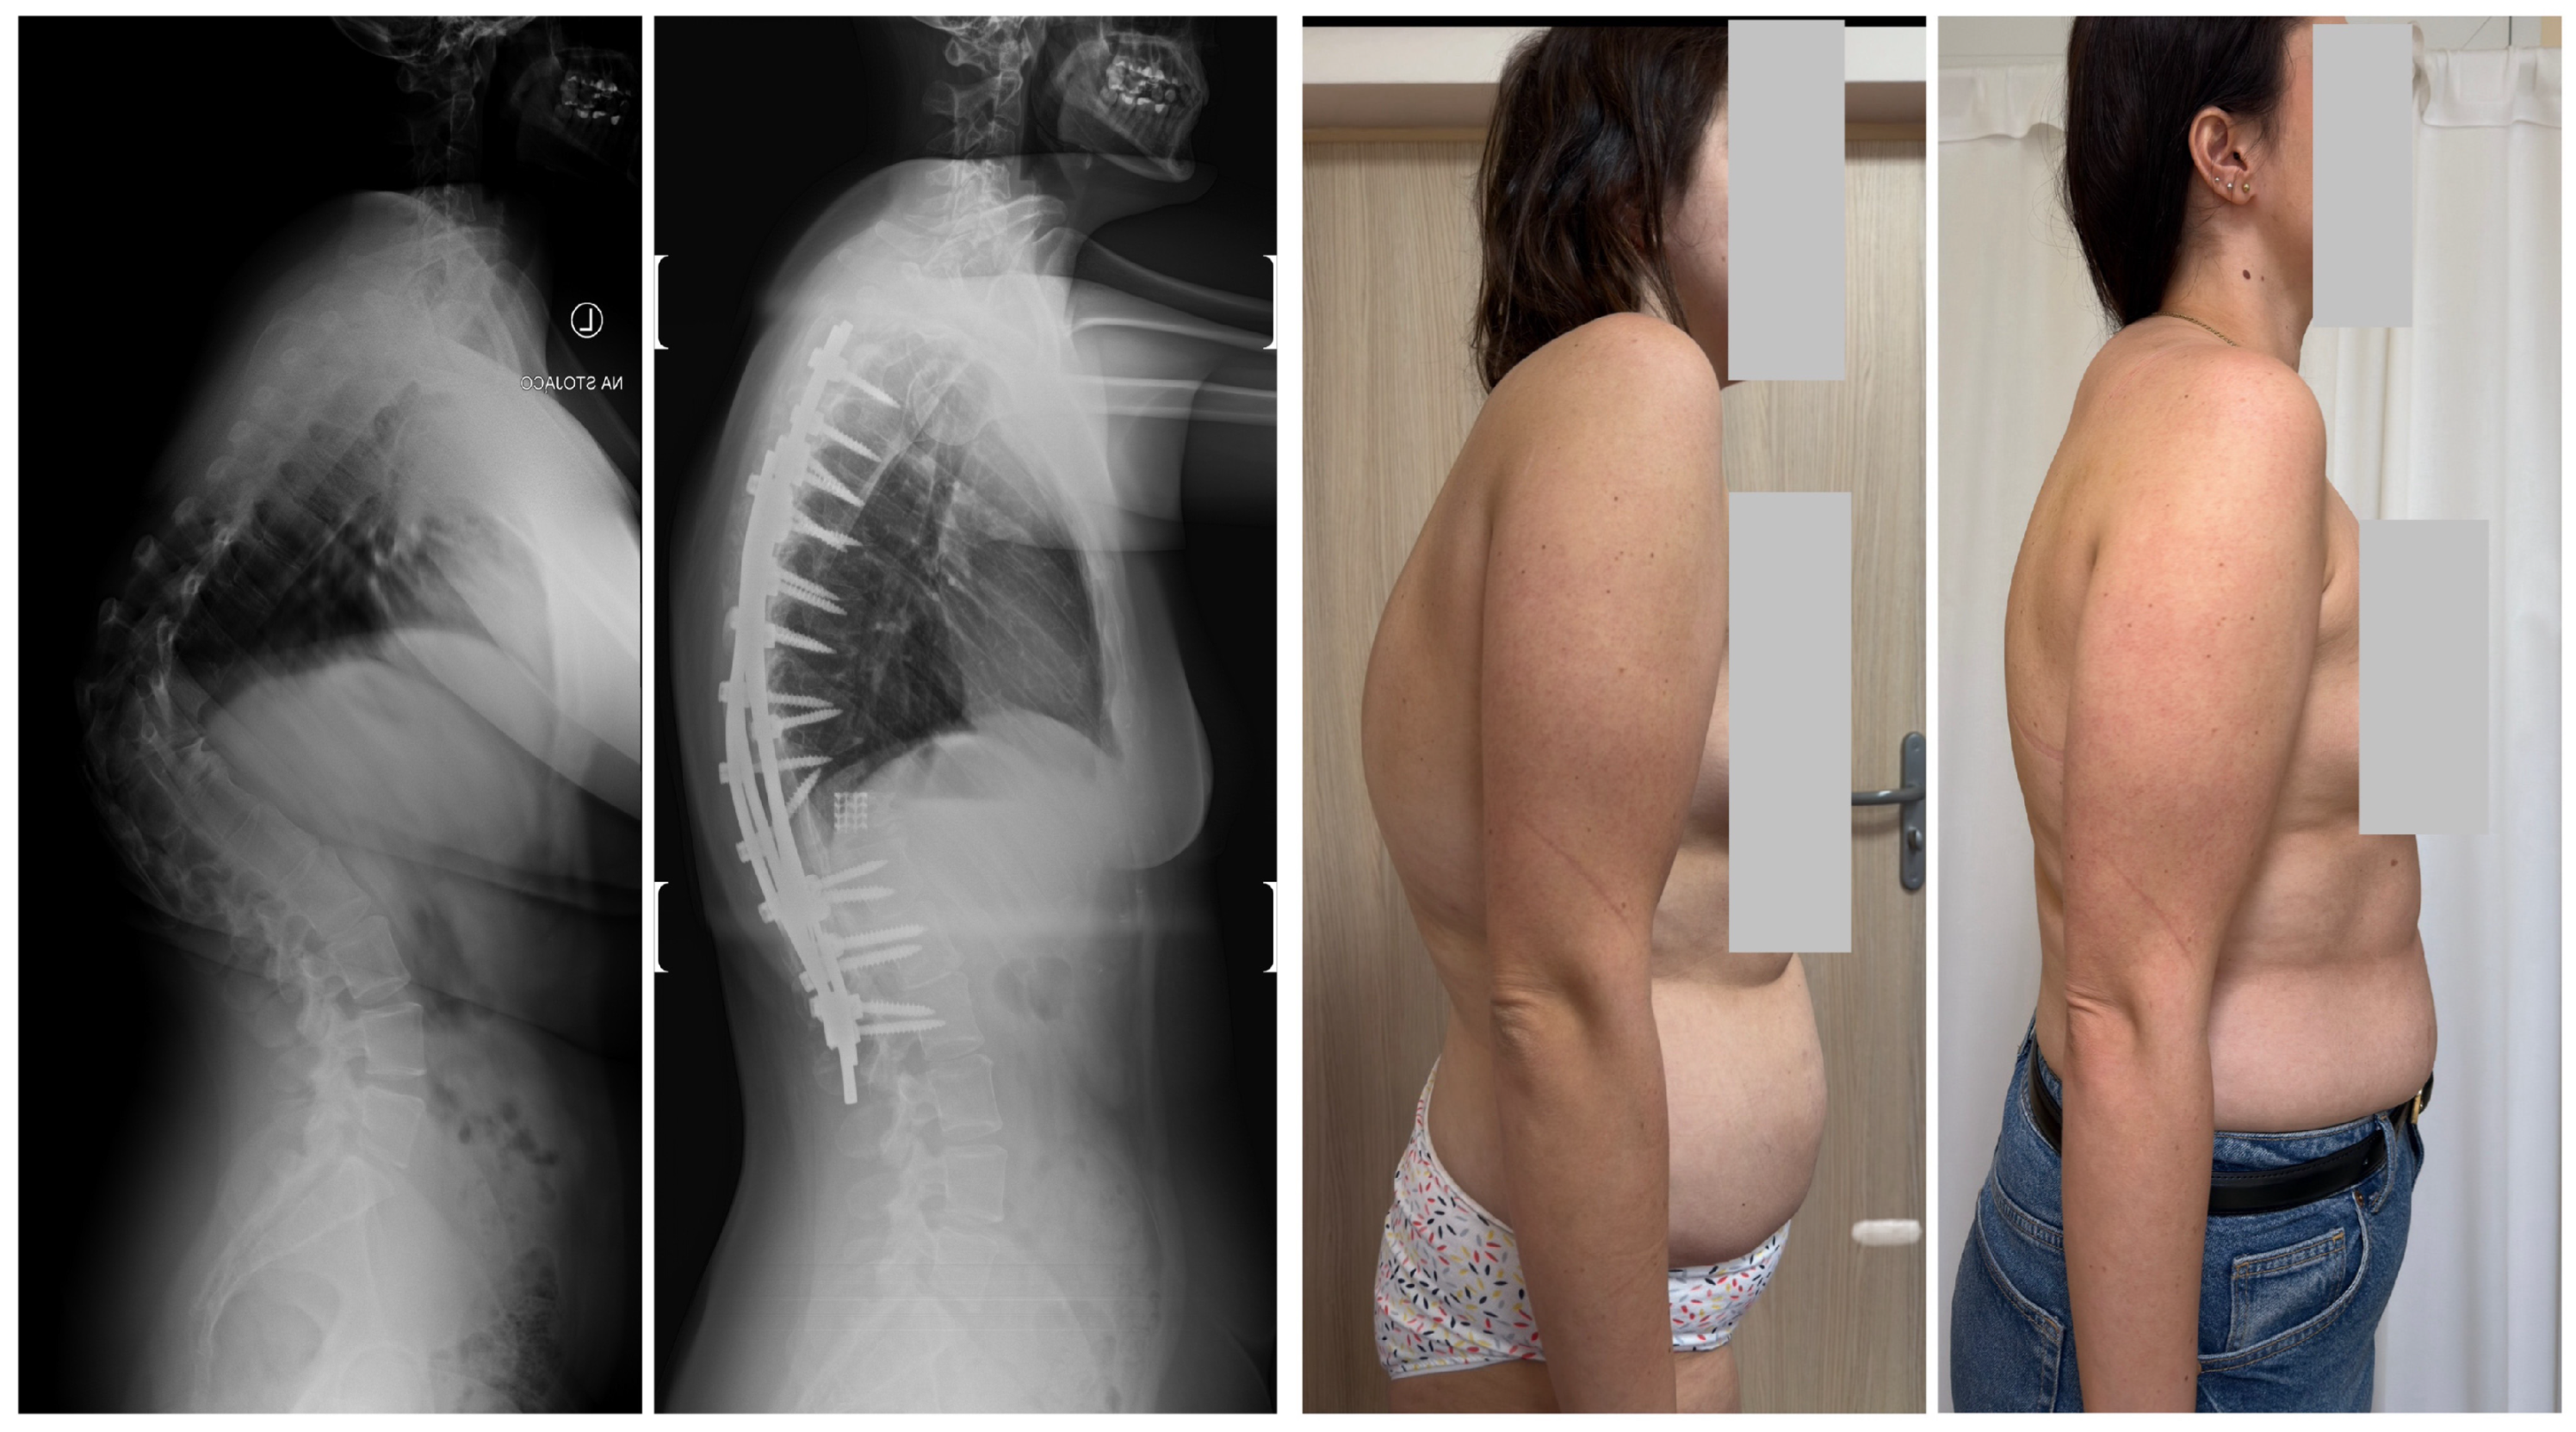

- Suk, S.I.; Chung, E.R.; Kim, J.H.; Kim, S.S.; Lee, J.S.; Choi, W.K. Posterior vertebral column resection for severe rigid scoliosis. Spine 2005, 30, 1682–1687. [Google Scholar] [CrossRef] [PubMed]

- Suk, S.I.; Kim, J.H.; Kim, W.J.; Lee, S.M.; Chung, E.R.; Nah, K.H. Posterior vertebral column resection for severe spinal deformities. Spine 2002, 27, 2374–2382. [Google Scholar] [CrossRef] [PubMed]

- Grabala, P.; Fani, N.; Gregorczyk, J.; Grabala, M. Posterior-only T11 vertebral column resection for pediatric congenital kyphosis surgical correction. Medicina 2024, 60, 897. [Google Scholar] [CrossRef] [PubMed]

- Asunis, E.; Cini, C.; Martikos, K.; Vommaro, F.; Evangelisti, G.; Griffoni, C.; Gasbarrini, A. Efficacy and Risks of Posterior Vertebral Column Resection in the Treatment of Severe Pediatric Spinal Deformities: A Case Series. J. Clin. Med. 2025, 14, 374. [Google Scholar] [CrossRef]

- Grabala, P.; Helenius, I.J.; Buchowski, J.M.; Shah, S.A. The efficacy of a posterior approach to surgical correction for neglected idiopathic scoliosis: A comparative analysis according to health-related quality of life, pulmonary function, back pain and sexual function. Children 2023, 10, 299. [Google Scholar] [CrossRef]